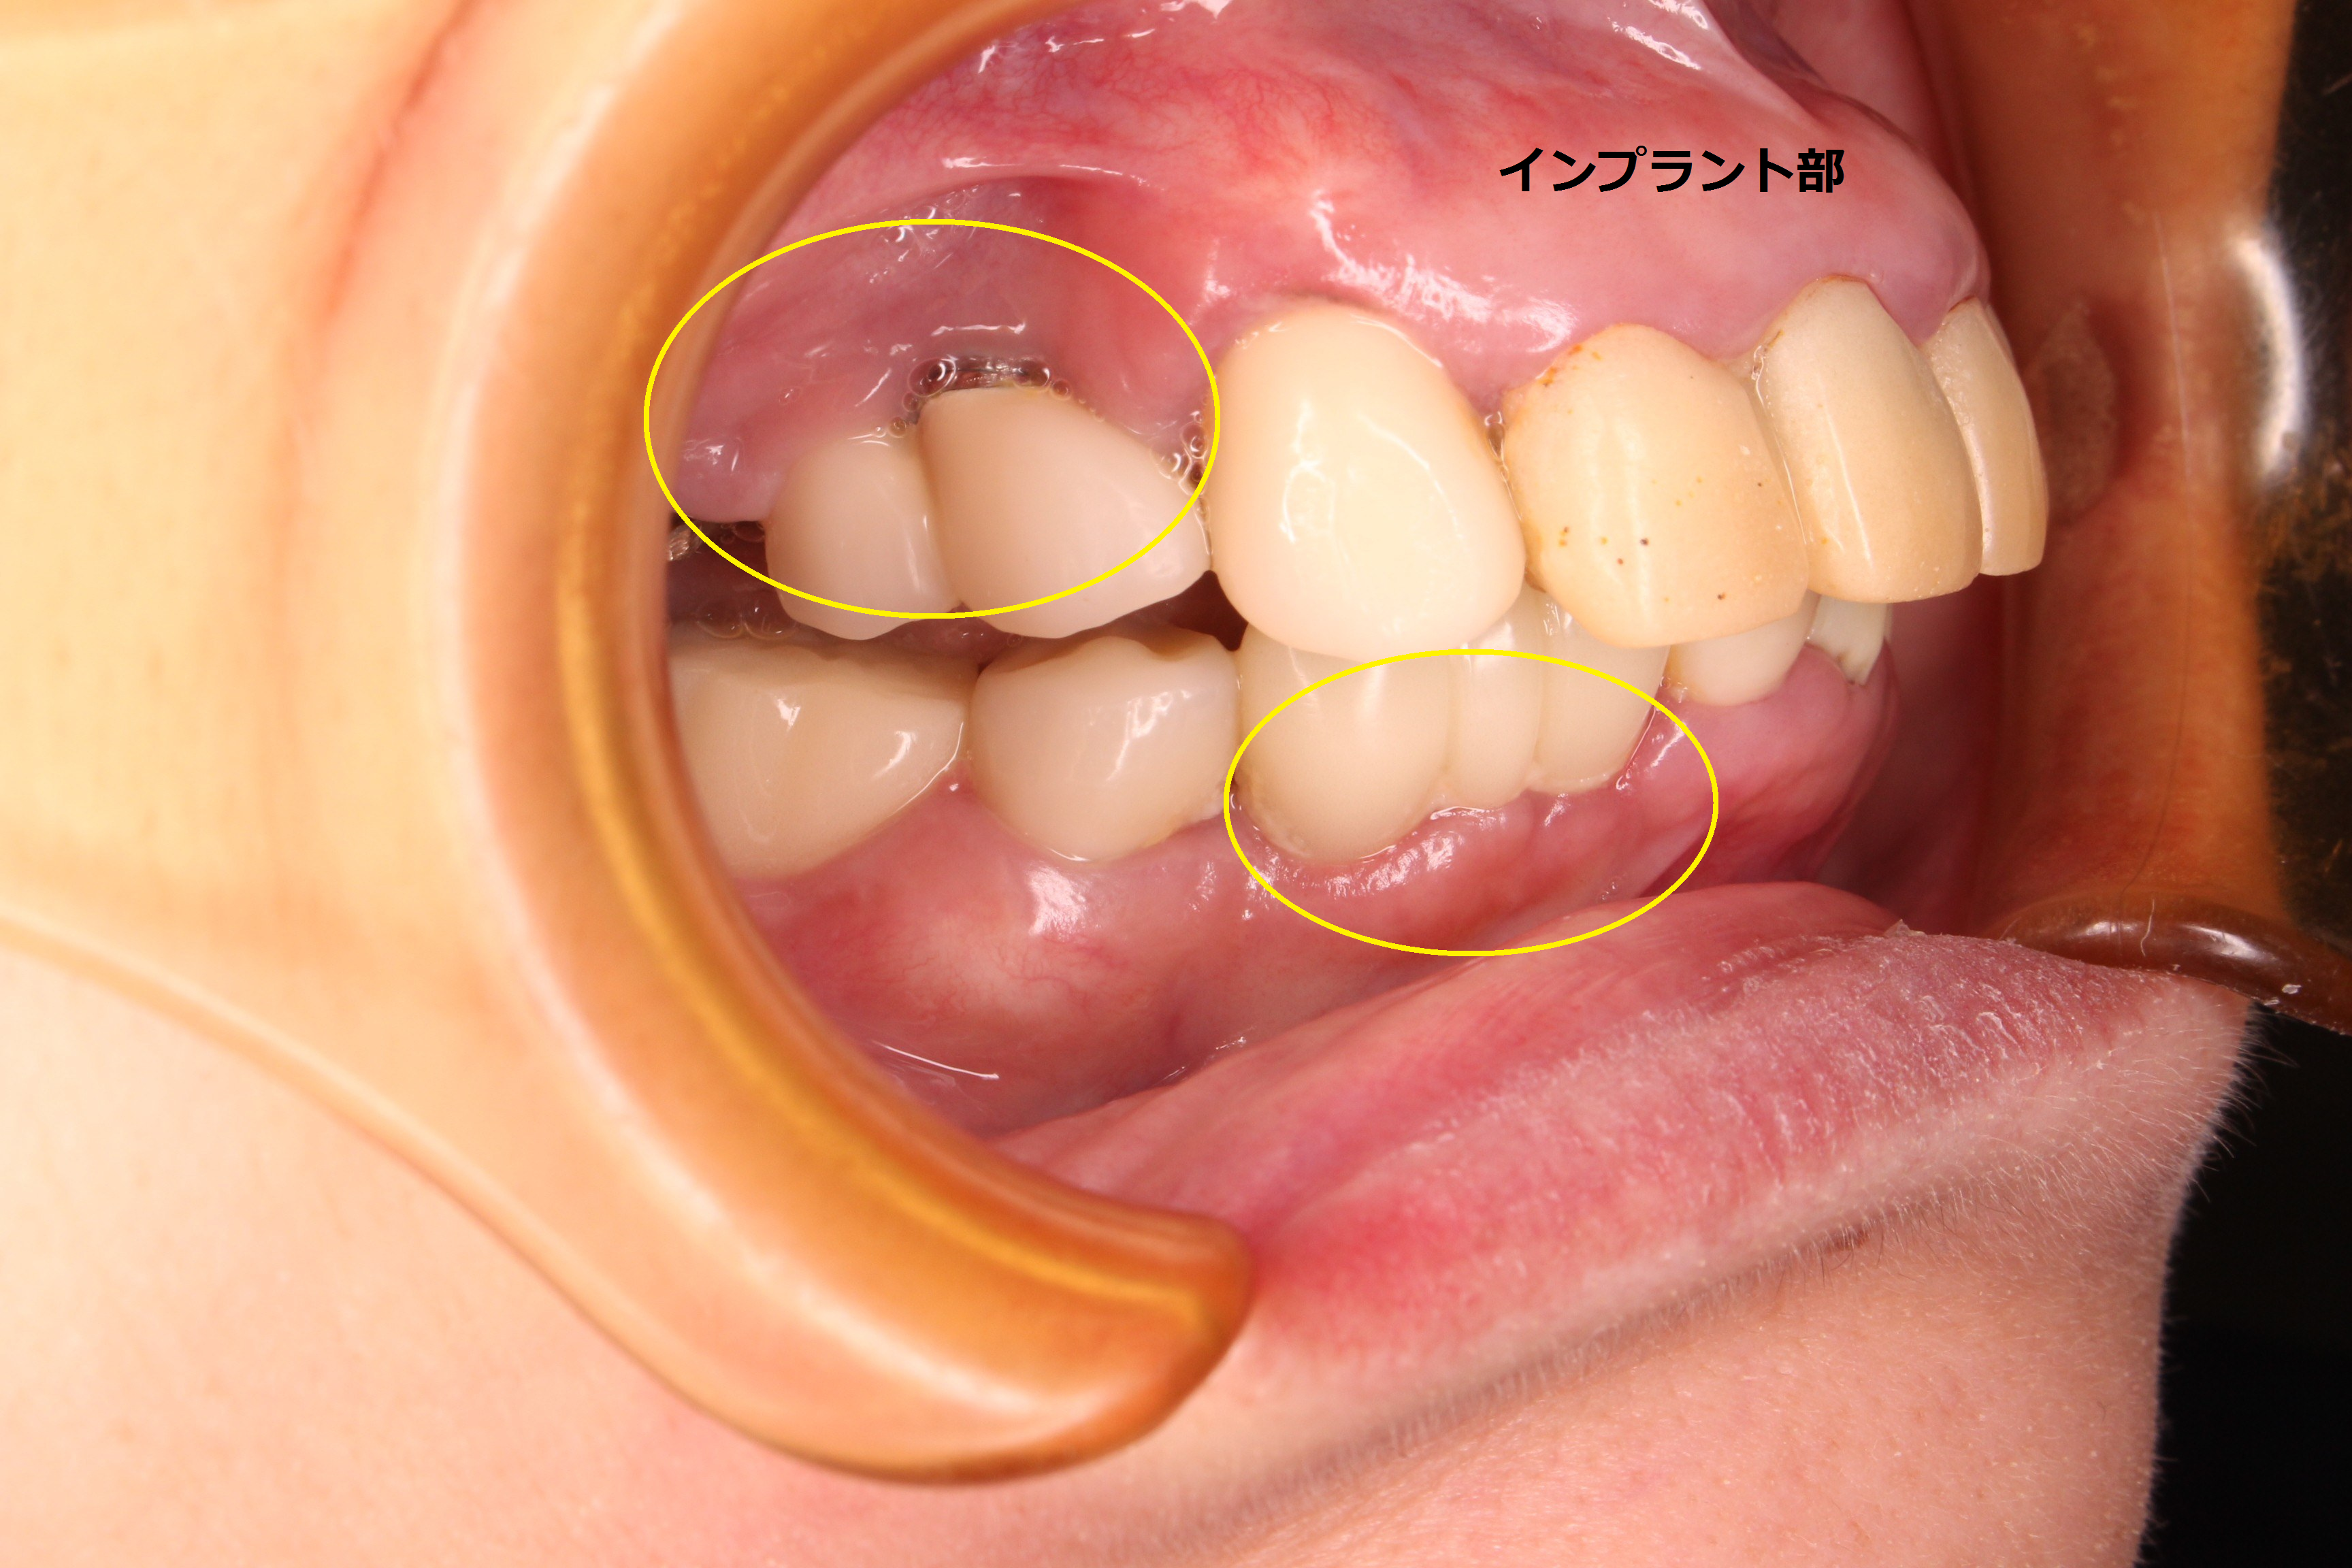

他院にて、数年前にインプラントを埋入してあります。

初診時 口腔内写真

全体的に炎症(発赤、腫脹、出血、排膿等)が広がっており、数年前に他院で入れたインプラント部の周辺歯肉も腫れ上がり、排膿していました。

ほぼ全ての歯に被せ物等の治療がしてあることからも、歯の治療で苦労してきたことが伺えます。